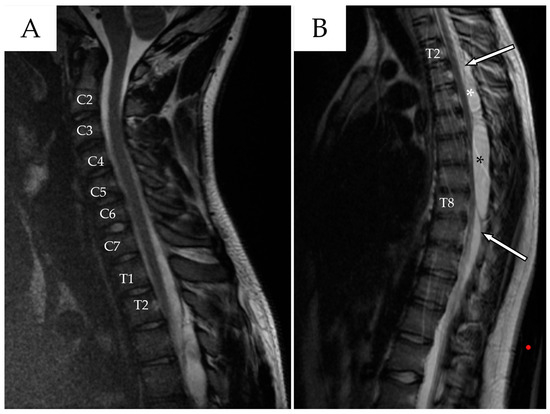

Whole-spine contrast-enhanced Magnetic Resonance Imaging (ceMRI) demonstrated a posterior, extradural intraspinal lesion extending from T2 to T8, causing significant compression of the dural sac and spinal cord (Figure 1). The lesion was formed by two components: a cranial one (T2–T4) and a larger caudal one (T5–T8). The area of maximal spinal cord compression was identified at T7–T8, where subtle intramedullary T2 hyperintensity was observed, suggestive of early spinal cord changes consistent with possible myelopathy (Figure 2). The lesion appeared hyperintense on T2-weighted images, isointense with CSF, and showed no contrast enhancement—findings consistent with a spinal arachnoid cyst.

Figure 1. (A) Cervical spine ceMRI, sagittal section, TSE T2-WI. The cranial portion of the SAC is visible at the T2 level. To facilitate counting, the cervical vertebrae and the first two thoracic vertebrae are marked with their corresponding names. (B) Thoracic spine ceMRI, sagittal section, TSE T2-WI. The SAC is visible in its entirety, composed of a smaller cranial portion (T2–T4, white asterisk) and a larger caudal portion (T5–T8, black asterisk). The dural sac is easily identifiable (white arrows with black outlines), confirming the extradural location.

Finally, MRI at 1 week after surgery showed a reduction in size of the pseudomeningocele at the T2–T4 level, along with decreased overall spinal cord compression and almost complete resolution of the caudal pseudomeningocele (Figure 9). The patient remained neurologically stable with mild improvement and no new deficits were observed.

Figure 9. Sagittal T2-weighted MRI performed 7 days after the last surgery, which included percutaneous repair of the dural leak. The result of the blood patch is visible in the upper portion of the spinal arachnoid cavity (white arrow). A marked reduction in the cranial pseudomeningocele (black asterisk) is noted, along with near-complete resolution of the inferior pseudomeningocele (white asterisk).